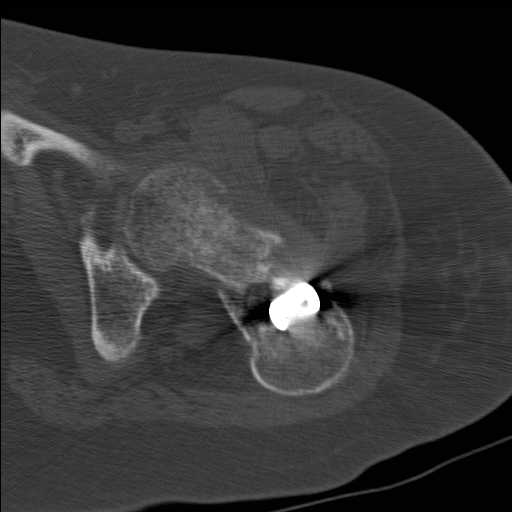

Перелом шейки бедра у девушки 19 лет. Чем лучше помочь?

Добрый день уважаемые коллеги. Во такая ситуация. Девушка 19 лет травму

получила в мае 2016г( изолированная травма, трансцервикальный перелом

шейки левого бедра). Соматически здорова. Лечилась по месту жительства

скелетным вытяжением в течении 1 месяца. Затем переведена в наше

учреждение. 18 июня выполнена операция, детали где , кто и как уточнять

не имеет смысла( из протокола операции: выполнялась передняя артротомия,

репозиция под визуальным контролем) . Учитывая характер выполненного

остеосинтеза, после операции постельный режим 6 недель. Снимки в

хронологии все выкладываю. КТ контроль сделан 2.09.16.  для оценки

состояния  головки бедра. Помогите, определиться с дальнейшей тактикой.